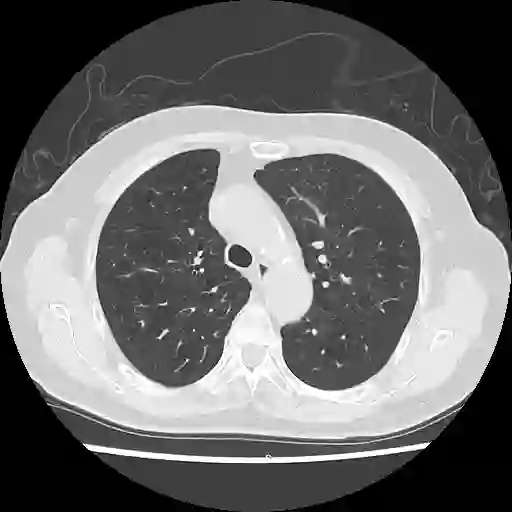

We propose a novel continual self-supervised learning (CSSL) framework for simultaneously learning diverse features from multi-window-obtained chest computed tomography (CT) images and ensuring data privacy. Achieving a robust and highly generalizable model in medical image diagnosis is challenging, mainly because of issues, such as the scarcity of large-scale, accurately annotated datasets and domain shifts inherent to dynamic healthcare environments. Specifically, in chest CT, these domain shifts often arise from differences in window settings, which are optimized for distinct clinical purposes. Previous CSSL frameworks often mitigated domain shift by reusing past data, a typically impractical approach owing to privacy constraints. Our approach addresses these challenges by effectively capturing the relationship between previously learned knowledge and new information across different training stages through continual pretraining on unlabeled images. Specifically, by incorporating a latent replay-based mechanism into CSSL, our method mitigates catastrophic forgetting due to domain shifts during continual pretraining while ensuring data privacy. Additionally, we introduce a feature distillation technique that integrates Wasserstein distance-based knowledge distillation (WKD) and batch-knowledge ensemble (BKE), enhancing the ability of the model to learn meaningful, domain-shift-robust representations. Finally, we validate our approach using chest CT images obtained across two different window settings, demonstrating superior performance compared with other approaches.

翻译:我们提出了一种新颖的持续自监督学习框架,用于同时从多窗位获取的胸部计算机断层扫描图像中学习多样化特征,并确保数据隐私。在医学影像诊断中构建鲁棒且高度可泛化的模型具有挑战性,主要源于大规模精确标注数据集的稀缺性以及动态医疗环境中固有的领域偏移问题。具体而言,在胸部CT中,这些领域偏移常由针对不同临床目的优化的窗位设置差异引起。以往的持续自监督学习框架通常通过复用历史数据来缓解领域偏移,但由于隐私限制,这种方法往往不切实际。我们的方法通过在未标注图像上进行持续预训练,有效捕捉不同训练阶段中已有知识与新信息之间的关联,从而应对这些挑战。具体而言,通过将基于潜在重放的机制融入持续自监督学习,我们的方法在确保数据隐私的同时,缓解了持续预训练中因领域偏移导致的灾难性遗忘。此外,我们引入了一种特征蒸馏技术,该技术整合了基于Wasserstein距离的知识蒸馏与批次知识集成,增强了模型学习具有意义且对领域偏移鲁棒的表征能力。最后,我们使用两种不同窗位设置获取的胸部CT图像验证了所提方法,结果表明其性能优于其他现有方法。